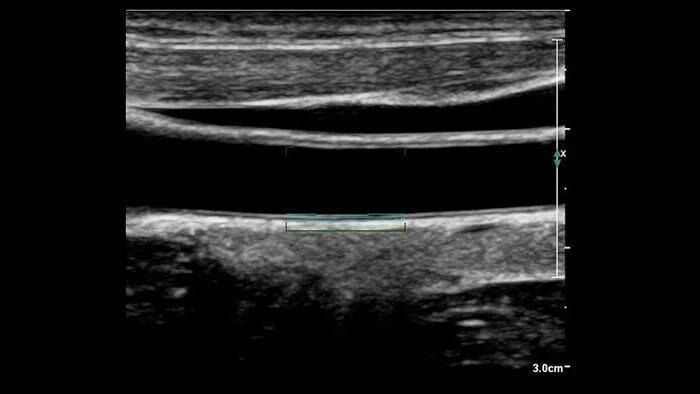

US Q-App Intima Media Thickness (IMT)

Support in determining cardiovascular disease risk

US Q-App Intima Media Thickness (IMT) provides easy and consistent measurement of intima media thickness in carotids and other superficial vessels. Report IMT values and append them to patient reports.

Benefits

- Automated measurement technique on user-selected frames.

- Selector chart to record location and side of vessel where the IMT is measured.

- Quick optimization for thin or thick intima media complexes.

- User-adjustable region of interest.

- User-defined measurement capability.

- Compatible with Philips EPIQ, Affiniti, iE33, iU22, CX50, HD15, HD11, HD7, EnVisor C.0 ultrasound systems.